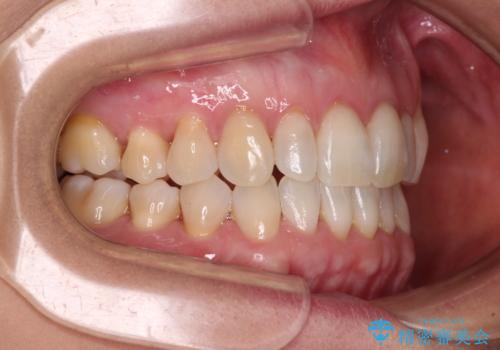

- 前歯の上下スペースによる食べにくさを気にして来院された患者様です。

インビザラインにより上下の前歯の隙間を閉じていくこととしました。

舌の突出癖があると上下前歯にスペースが開くため、矯正治療を機会に舌癖を改善するトレーニングを行ってもらい、矯正治療後の後戻りを防止するように指導しています。